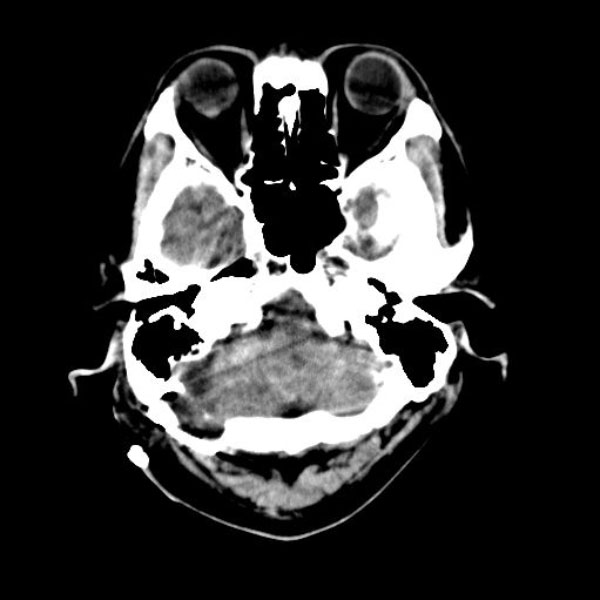

手術後

(CT)